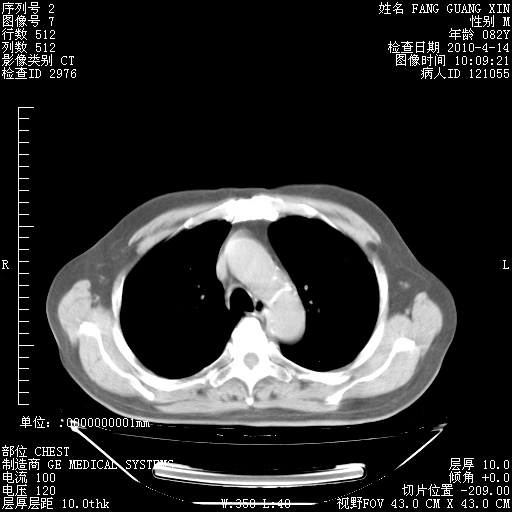

4月14日肺部CT

23.JPG

24.JPG

25.JPG

26.JPG